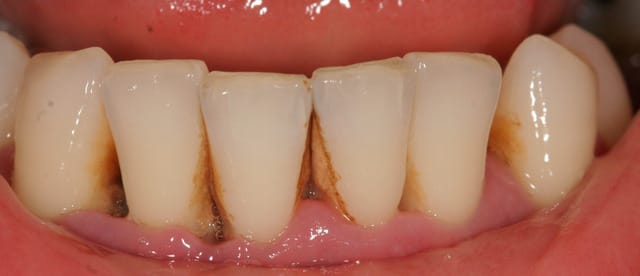

Paro ultra agressive chez une jeune femme de 30 ans.

Dans toute cette période, je n'ai pour ainsi dire quasiment jamais eu de cas de parodontite agressive aussi importante que celle ci.

la patiente est très jolie, elle a 30 ans, a consulté deux ou trois dentiste en l'espace de 10 ans, le dernier détartrage date il y a trois ans et il n'a pas été terminée apparemment car la patiente avait trop de douleurs, et aujourd'hui elle est adressée par un hôpital parisien qui devait lui poser des implants et qui devant la panoramique a renoncé sans pour autant la diriger correctement.

on est clairement devant une parodontite agressive généralisée avec comme facteur de risque le Tabac et un facteur aggravant l'occlusion ...

...il y a autre chose: trés peu de dents postérieures soutiennent l'occlusion, et on est en début d'effondrement, avec les antérieures qui commencent à partir en éventail.